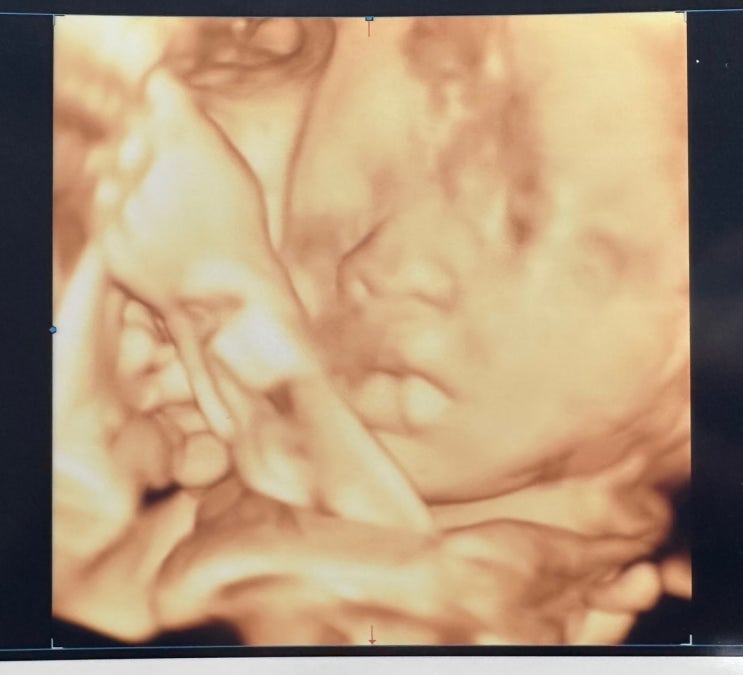

[만삭촬영 ]임신29주차, 창원베일리수, 조리원연계 만삭촬영

안녕하세요 글을 써야지 하다가 미루다보니 벌써 내일이면 30주가 되네요! 요즘엔 인기있는 조리원은 예약...